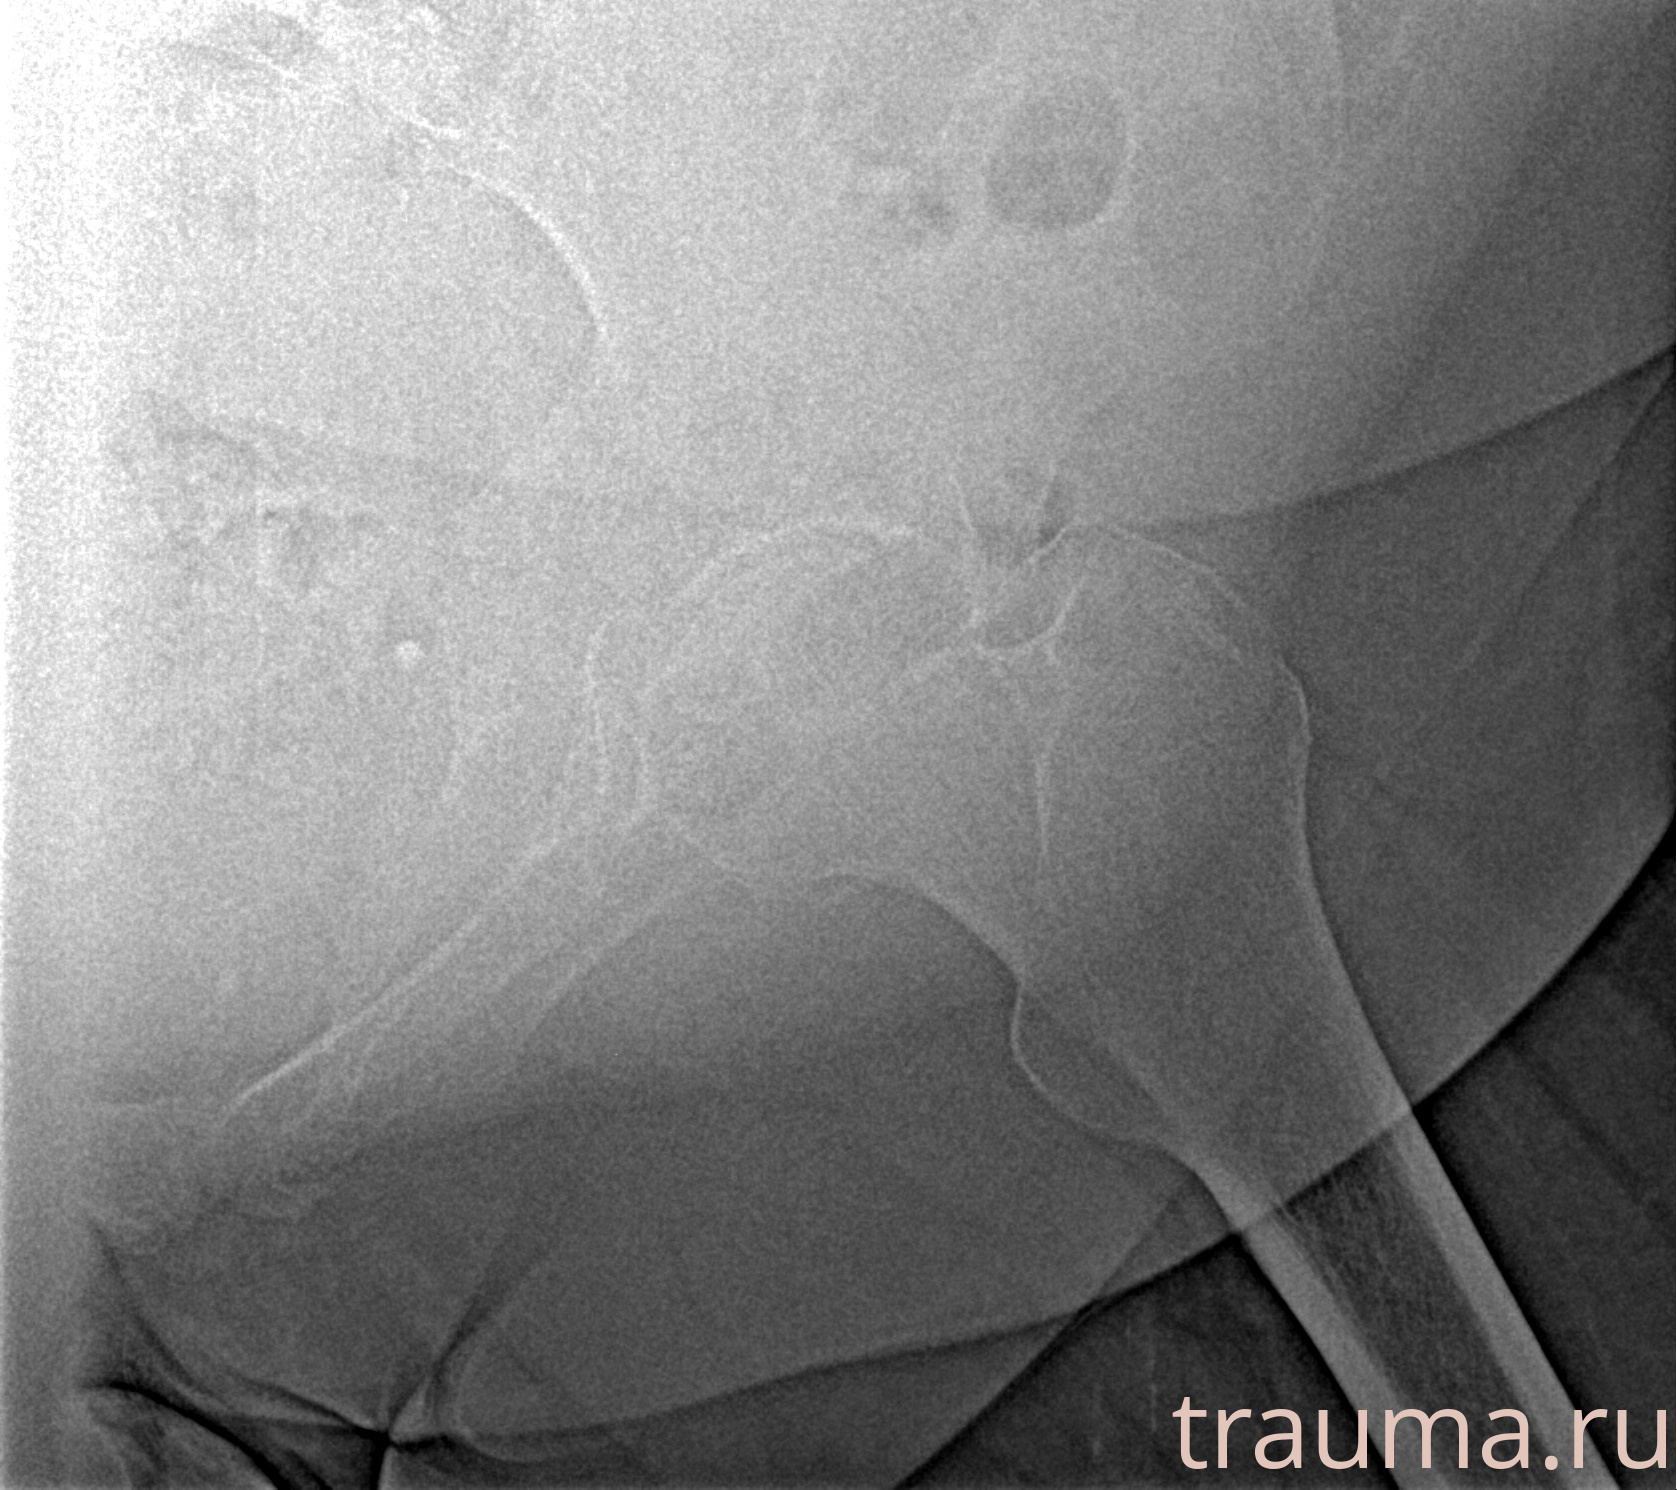

Рентгенограммы

Рентген на дому: по вашему адресу приезжает врач-рентгенолог, травматолог-ортопед с мобильным рентгеновским аппаратом, проводит диагностику травмы или заболевания, делает необходимые рентгенограммы, дает рекомендации по дальнейшему лечению. Получить качественные снимки в домашних условиях возможно благодаря уникальной методике, разработанной МосРентген Центром для института  Склифосовского